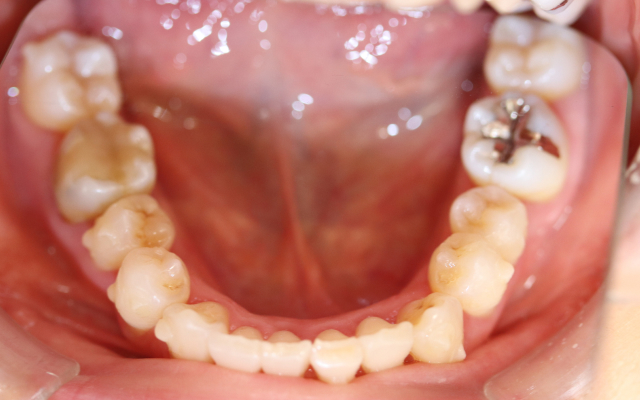

case. 01

インビザライン矯正の症例

before

after

30代 女性 叢生(そうせい), 交叉咬合(こうさこうごう)

施術概要

マウスピース矯正は、1日20時間以上マウスピースを装着する事により歯並びの矯正を行う事が出来る治療です。歯を動かしていく段階で1週間毎に新しいアライナーに交換し、少しずつ歯並びを綺麗にしていきます。

金額

616,000円(税込)

期間・回数

1年5ヶ月

リスク・副作用

全ての方で、疼痛、咬合痛、歯根吸収、歯根露出が生じる可能性があり。マウスピースを装着できなかった場合、予定通りに歯が動かない可能性があります。